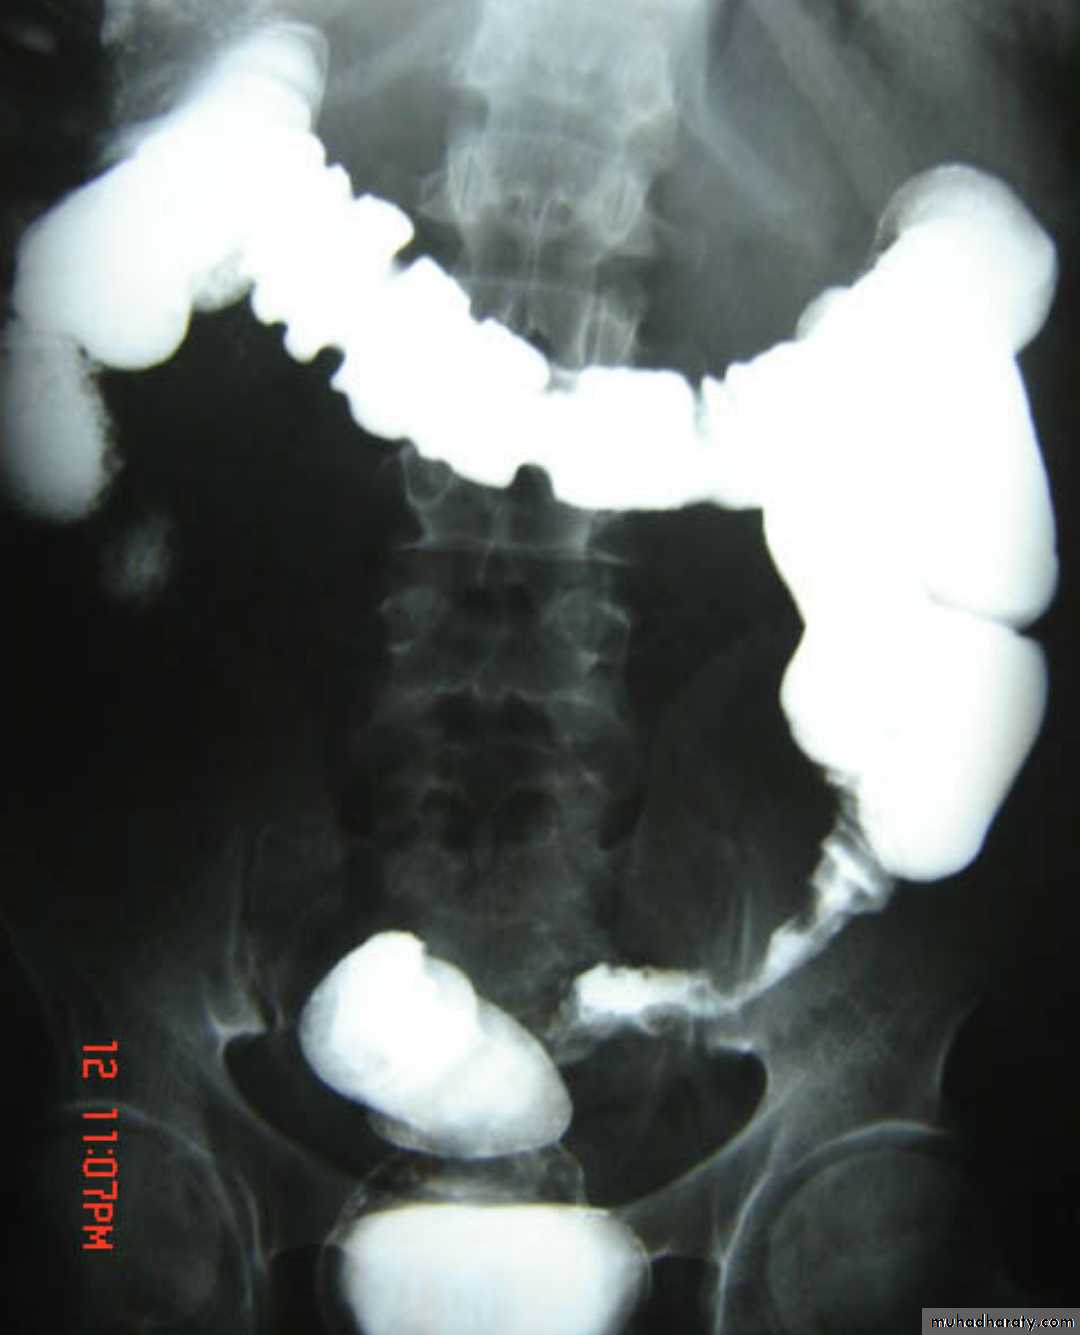

Colonic diverticulosis

refers to the presence of multiple diverticula. It is quite distinct from diverticulitis which describes inflammation and infection of one or multiple diverticula.Radiographic features

Diverticula range in size from a few millimeters to a few centimetersBarium enema

Both single and double contrast barium enemas are able to demonstrate diverticula as barium-filled out-pouchings.